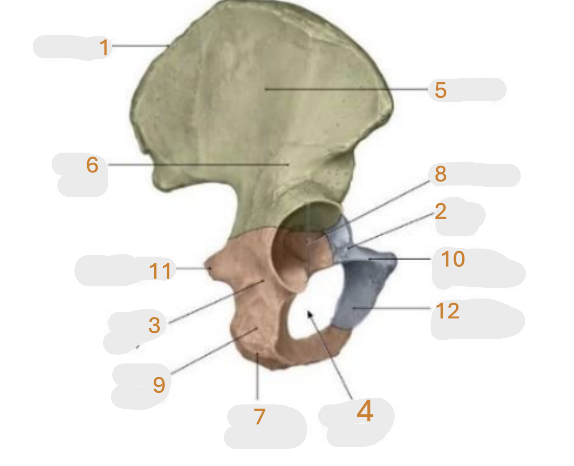

Where is the iliac crest

1

Where is the pubis body

2

Where is the ischium body

3

Where is the obturator foramen

4

Where is iliac wing

5

Where is the ilium body

6

Where is the ischial tuberosity

7

Where is the acetabulum

8

ischial ramus

9

Where is the superior pubic ramus

10

Where is the ischial spine

11

Where is the inferior pubic ramus

12